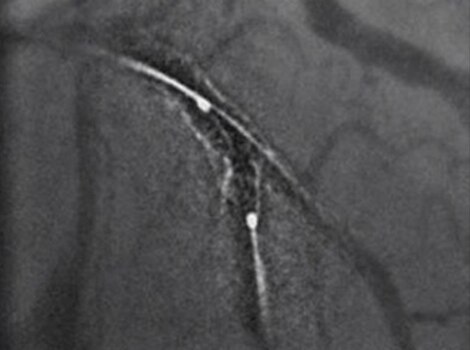

For patients sent for revascularization in the catheterization lab, attempts are made to rapidly access the culprit artery and complete further assessment of coronary tree. Rapid intervention can help minimize time to reperfusion from first medical contact.

Innova IGS 5 or Discovery IGS 7

Helps reduce use of contrast and dose with one of the industry’s highest ratings for Detective Quantum Efficiency (DQE).12

PCI ASSIST13

Help plan, assess and guide interventional procedures with improved visibility up to 85 percent in moving anatomy.